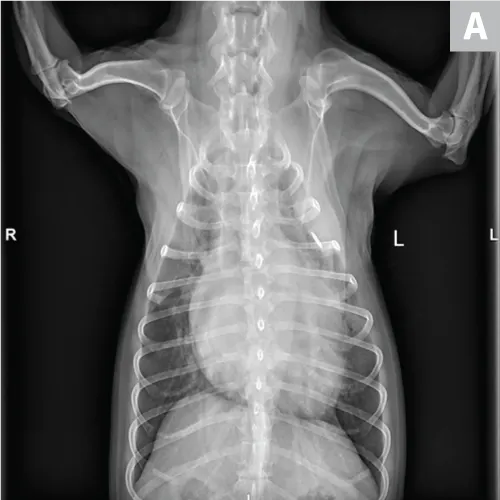

Pulmonary neoplasia may, on occasion, have a more diffuse nature. This is common with pulmonary lymphoma40 and is sometimes seen with carcinoma (author experience). Pulmonary lymphoma can have a rapid clinical course and mimic acute disorders. A diffuse, unstructured interstitial pattern is typically appreciated. Additionally, bronchointerstitial, alveolar, and nodular patterns may be observed (Figure 7).40

FIGURE 7

(A) Pulmonary lymphoma with a diffuse, patchy bronchointerstitial pattern confirmed on bronchoalveolar lavage and peripheral lymph node aspiration. (B) Pulmonary carcinoma with a diffuse, severe bronchointerstitial pattern confirmed on bronchoalveolar lavage and postmortem examination. Note: Pulmonary and hilar lymphadenopathy are not always present.